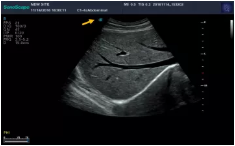

Mark點(diǎn):每一把探頭都有一個(gè)mark點(diǎn),是用于定位方向, mark點(diǎn)一側(cè)始終對應(yīng)著圖像S點(diǎn)(圖像箭頭標(biāo)識)一側(cè)。